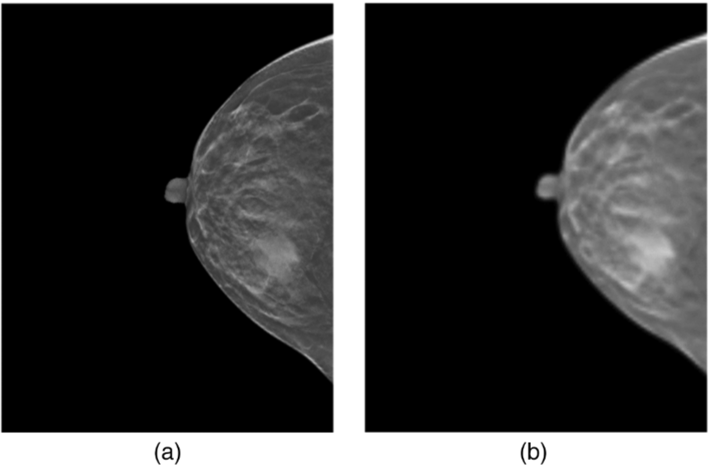

DBT Slice의 이미지 특성 상 해상도가 매우 높지만 Mass region이 해상도에 비해서 매우 작은 특징이 있습니다. 이러한 특징을 가지고 있는 DBT Slice 이미지를 그저 단순하게 Resizing 하게 되는 경우, 해상도 감소로 이어지는 원인이 됩니다. 좌측 이미지의 경우 원본 이미지에 해당하며 우측 이미지는 좌측 이미지에 대해서 단순한 Resizing을 활용한 결과입니다. 실제로도 해상도 측면에서 많은 Loss가 발생함을 확인할 수 있습니다.